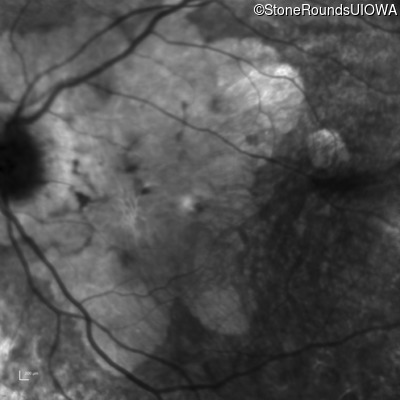

Foveal Hypoplasia (IIIG)

Highlighted Images

Diagnosis & molecular findings

Foveal Hypoplasia PAX6 Pro76Leu CCG>CTG   AD